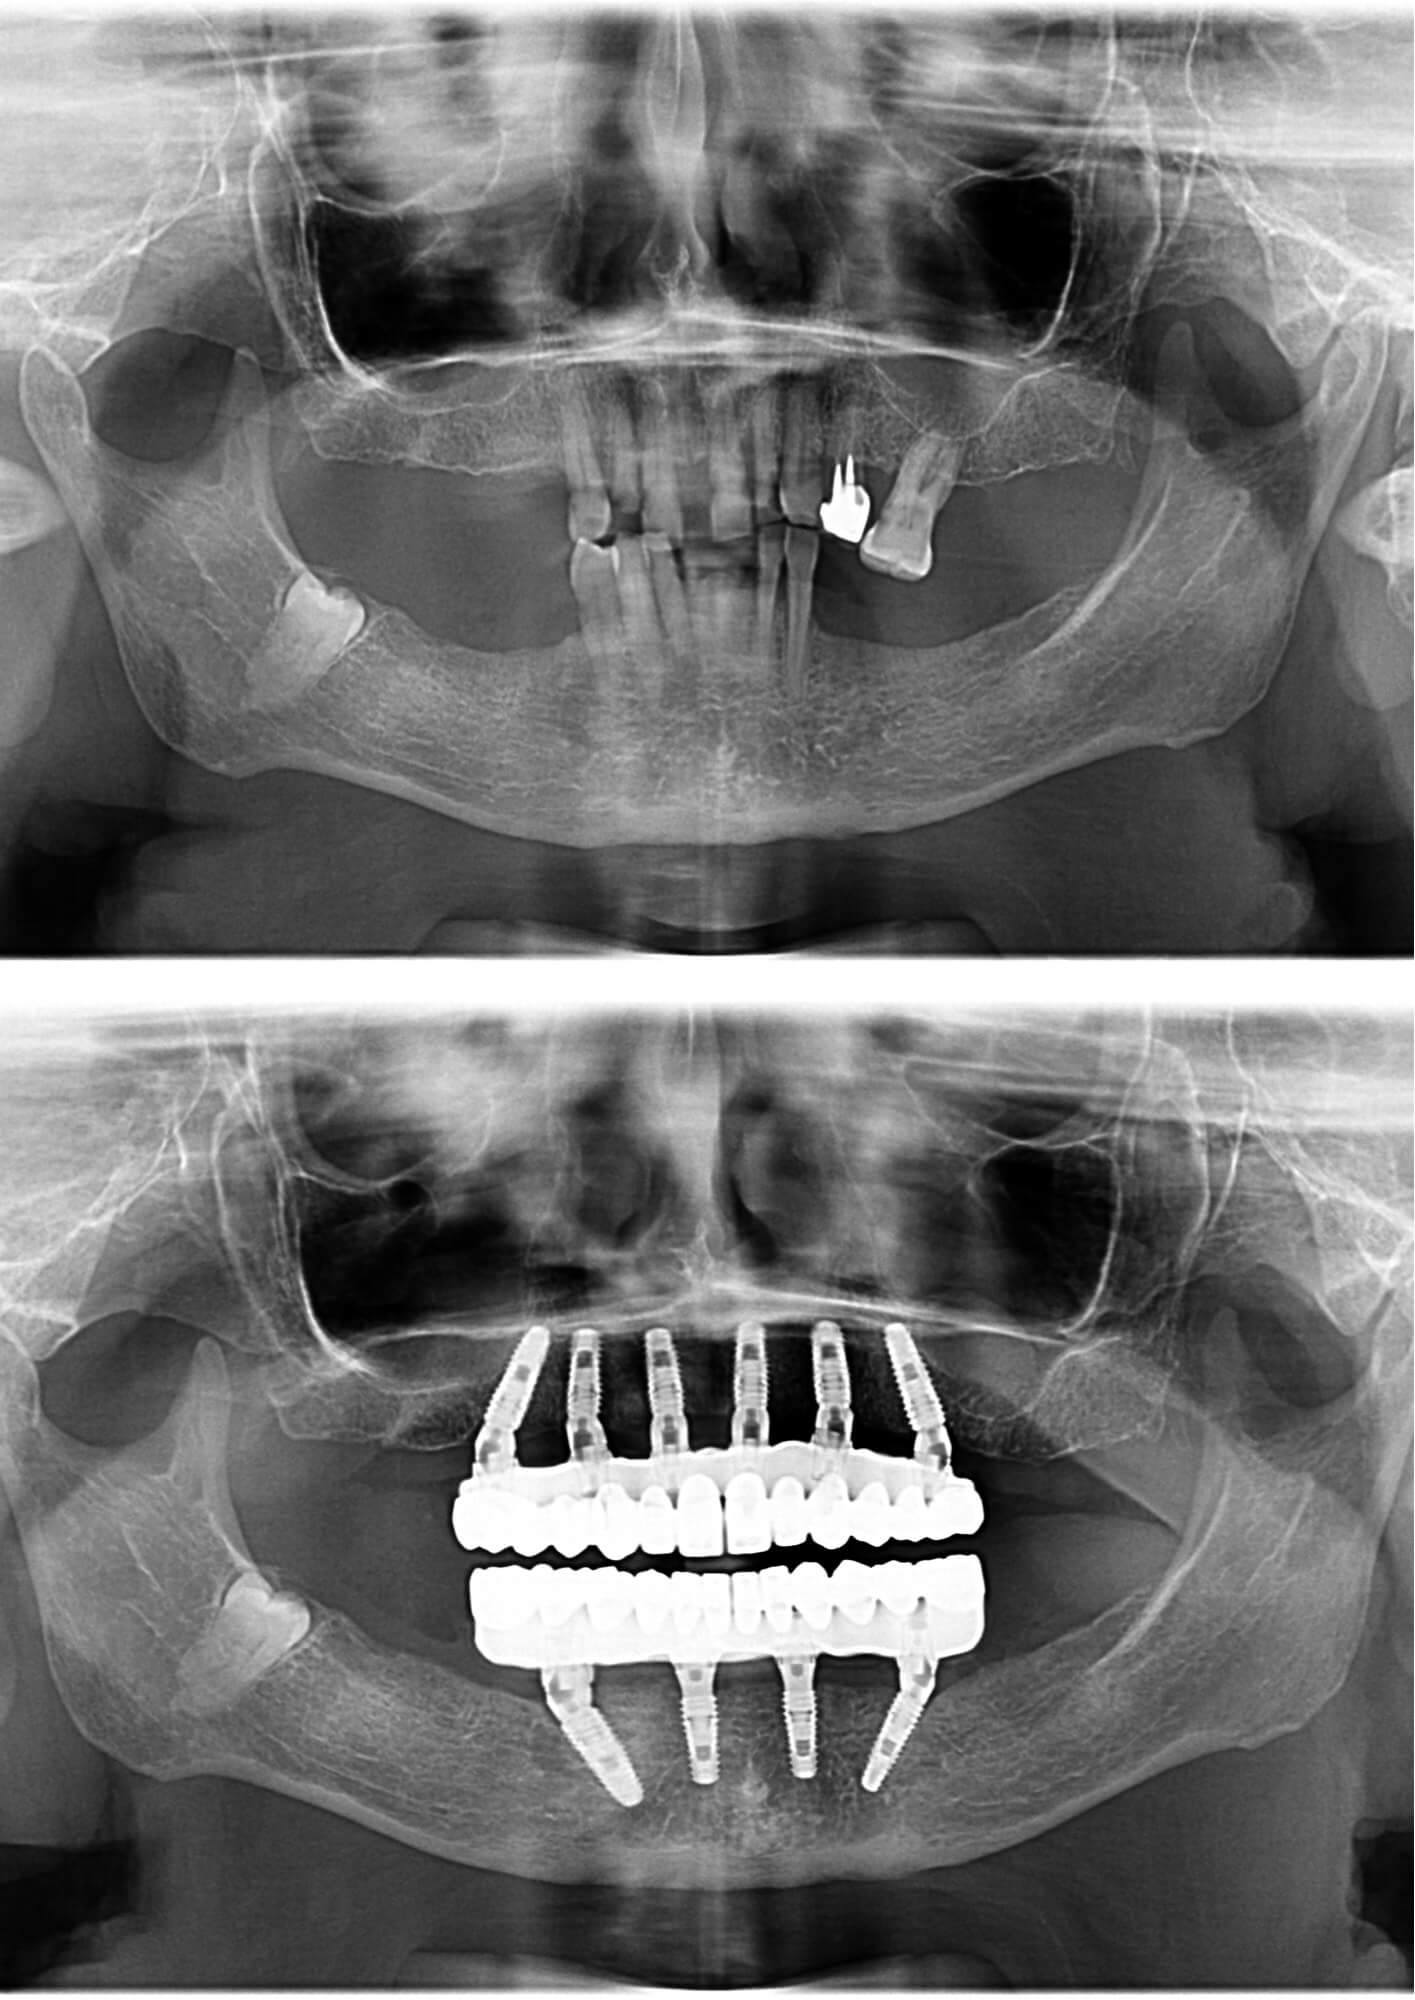

În radiografiile de mai jos, putem vedea schimbarea din punct de vedere clinic. Doamna A. mai avea doar câțiva dinți, care nu o mai ajutau să mănânce sau să zâmbească.

Doamna A. a beneficiat de 10 implanturi dentare după ce boala parodontală i-a distrus dantura atât la maxilar, cât și la mandibulă. O dată ce a ajuns în cadrul clinicii noastre, Dr Cazacu Corrado i-a expus cel mai bun plan de tratament.